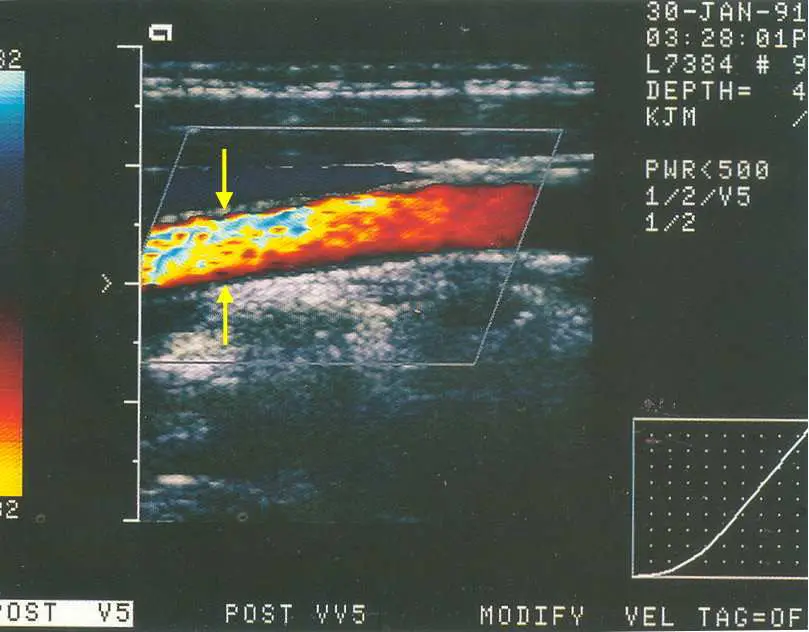

本題影像為頸動脈縱切面彩色都卜勒超音波(color Doppler sonogram of carotid artery, longitudinal view)。

影像中可見:

- 主要血流:血管腔內大部分區域呈橘紅色(red/orange),表示血流方向朝向探頭(toward transducer)

- 黃色箭號所指區域(影像左上方):在橘紅色血流區域的上方,出現一塊**藍色與紅色鑲嵌混雜(mosaic color pattern)**的彩色區塊,與主血流的均勻紅色形成強烈對比

這種「在同一血管內,血流方向並未真正改變,但彩色都卜勒顯示出反向色彩(紅→藍)」的現象,正是**混疊假影(aliasing artifact)**的典型表現。其發生原因是局部血流速度超過了儀器設定的 Nyquist 極限(= PRF/2),導致都卜勒頻移(Doppler shift)無法被正確取樣(undersampling),出現「卷疊(wrap-